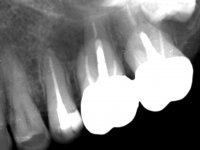

Male patient, 34 years old, non-smoker. Teeth 17 and 16 had extensive restorations with composite resin and placed intra-radicular posts. In the imaging examination, it was found that the endodontic treatment was not technically satisfactory, but had been asymptomatic for several years. The patient was rehabilitated with a 2-element bridge at 17 and 16 and 4 years later an abscess appeared in the apical area of 2.6. It had the 2.8 tooth included with a close relationship with the 2.7 root. During these 4 years there was no positional change of this tooth. After endodontic retreatment of teeth 27 and 26, an abscess appears again in the area of tooth 26, possibly associated with a root fracture. Given the history referred to in relation to tooth 26, it was considered a tooth with indicated extraction.

Teeth 17 and 16 were prepared for the fabrication of a 2-element Zr bridge. The impression was performed with a double mixing technique and a monolithic bridge in Zr was made in the laboratory. 4 years later, an abscess appeared in the apical area of tooth 26. It was decided to remove the bridge, remove the intra-radicular posts and retract the endodontic treatments of teeth 17 and 16. The removal of the bridge was carried out by making two cervical cavities. in the palatal area of the bridge and with a microluxator, disinsertion movements were performed. The intra-radicular posts were removed using fine drills and an ultrasound tip. The bridge was provisionally cemented and the patient was referred to a fellow endodontist for endodontic retreatment. After the retreatment, the intraradicular posts were placed again and the bridge was definitively cemented. One year later, a new abscess appears, possibly related to a root fracture. The bridge was sectioned between tooth 27 and 26 and tooth 26 was extracted and the crown of 27 was provisionally cemented. 3 months later, teeth 27 and 25 were prepared and a temporary bridge was made in dual polymerization resin. Then, an impression was made using the double mixing technique and a 3-element bridge in Zr was made in the laboratory. It was permanently cemented in the mouth with resin-reinforced glass ionomer cement.